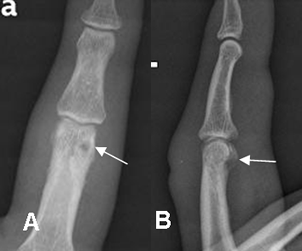

Fig 40. Osteomielitis crónica.

A: Rx AP y B: Rx lateral. Aumento en la densidad de la región epifisometafisiaria de la tibia, como secuelas de osteomielitis curada.

Fig 44. Osteomielitis crónica reagudizada.

A: Rx AP y B: Rx lateral. Episodios a repetición de osteomielitis, después de un trauma abierto. Prominencia en los tejidos blandos del 2º dedo. Hay aumento en la densidad de la falange proximal, con área radiolúcida y bien definida. Los cambios son compatibles con osteomielitis crónica.